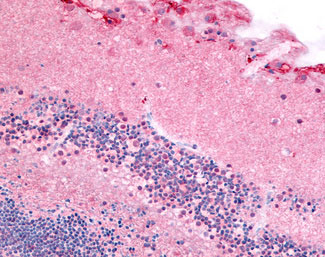

Anti-PDE6A / PDE6 Alpha antibody APR12778G IHC of human eye, retina. |